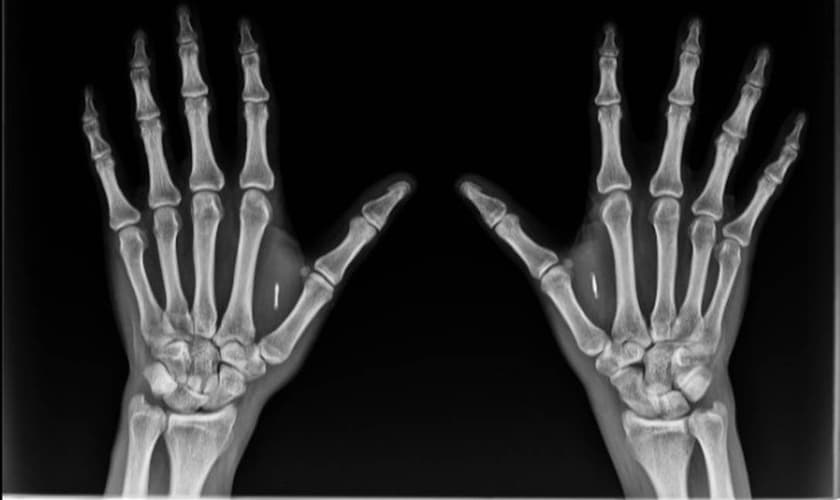

Ele próprio já tem dois chips instalados, um em cada mão, e explicou que os minúsculos dispositivos podem ajudar abrir portas e desbloquear códigos apenas aproximando as mãos de um sensor.

Bordini contou que o implante dos chips em suas mãos foi feito em 2017 e 2018 por motivos profissionais. colocou os chips por interesses profissionais: o primeiro para servir como um identificador e o segundo, para fazer leitura em smartphones mas também armazenar dados dentro dele. O dispositivo é envolto em vidro, o que impede oxidação e inflamação, além de armazenar 4 Kb de informações.

“Quando falamos de informações médicas, até pela capacidade do chip, não é armazenar toda sua vida médica, mas um resumo dos itens mais essenciais da sua vida: contatos de emergência, alergias, tipo sanguíneo, uso de medicamentos controlados. Se você perguntar para boa parte da população, ela não sabe qual é o tipo sanguíneo. Se alguém sofre um acidente e desmaia, você não sabe nada. São todas informações úteis”, afirmou.